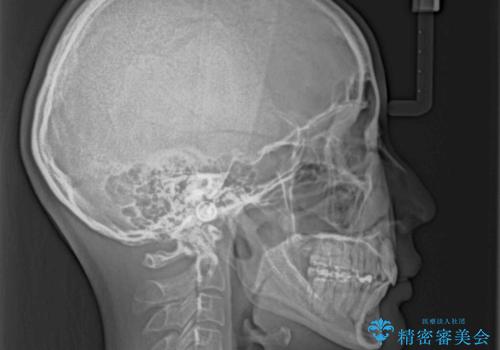

- 飛び出した前歯を気にして来院された患者様です。

口元を引っ込めるために上下左右の第一小臼歯4本を抜歯することとしました。

途中妊娠と出産がありましたが、予定よりも早く治療を終えることができました。